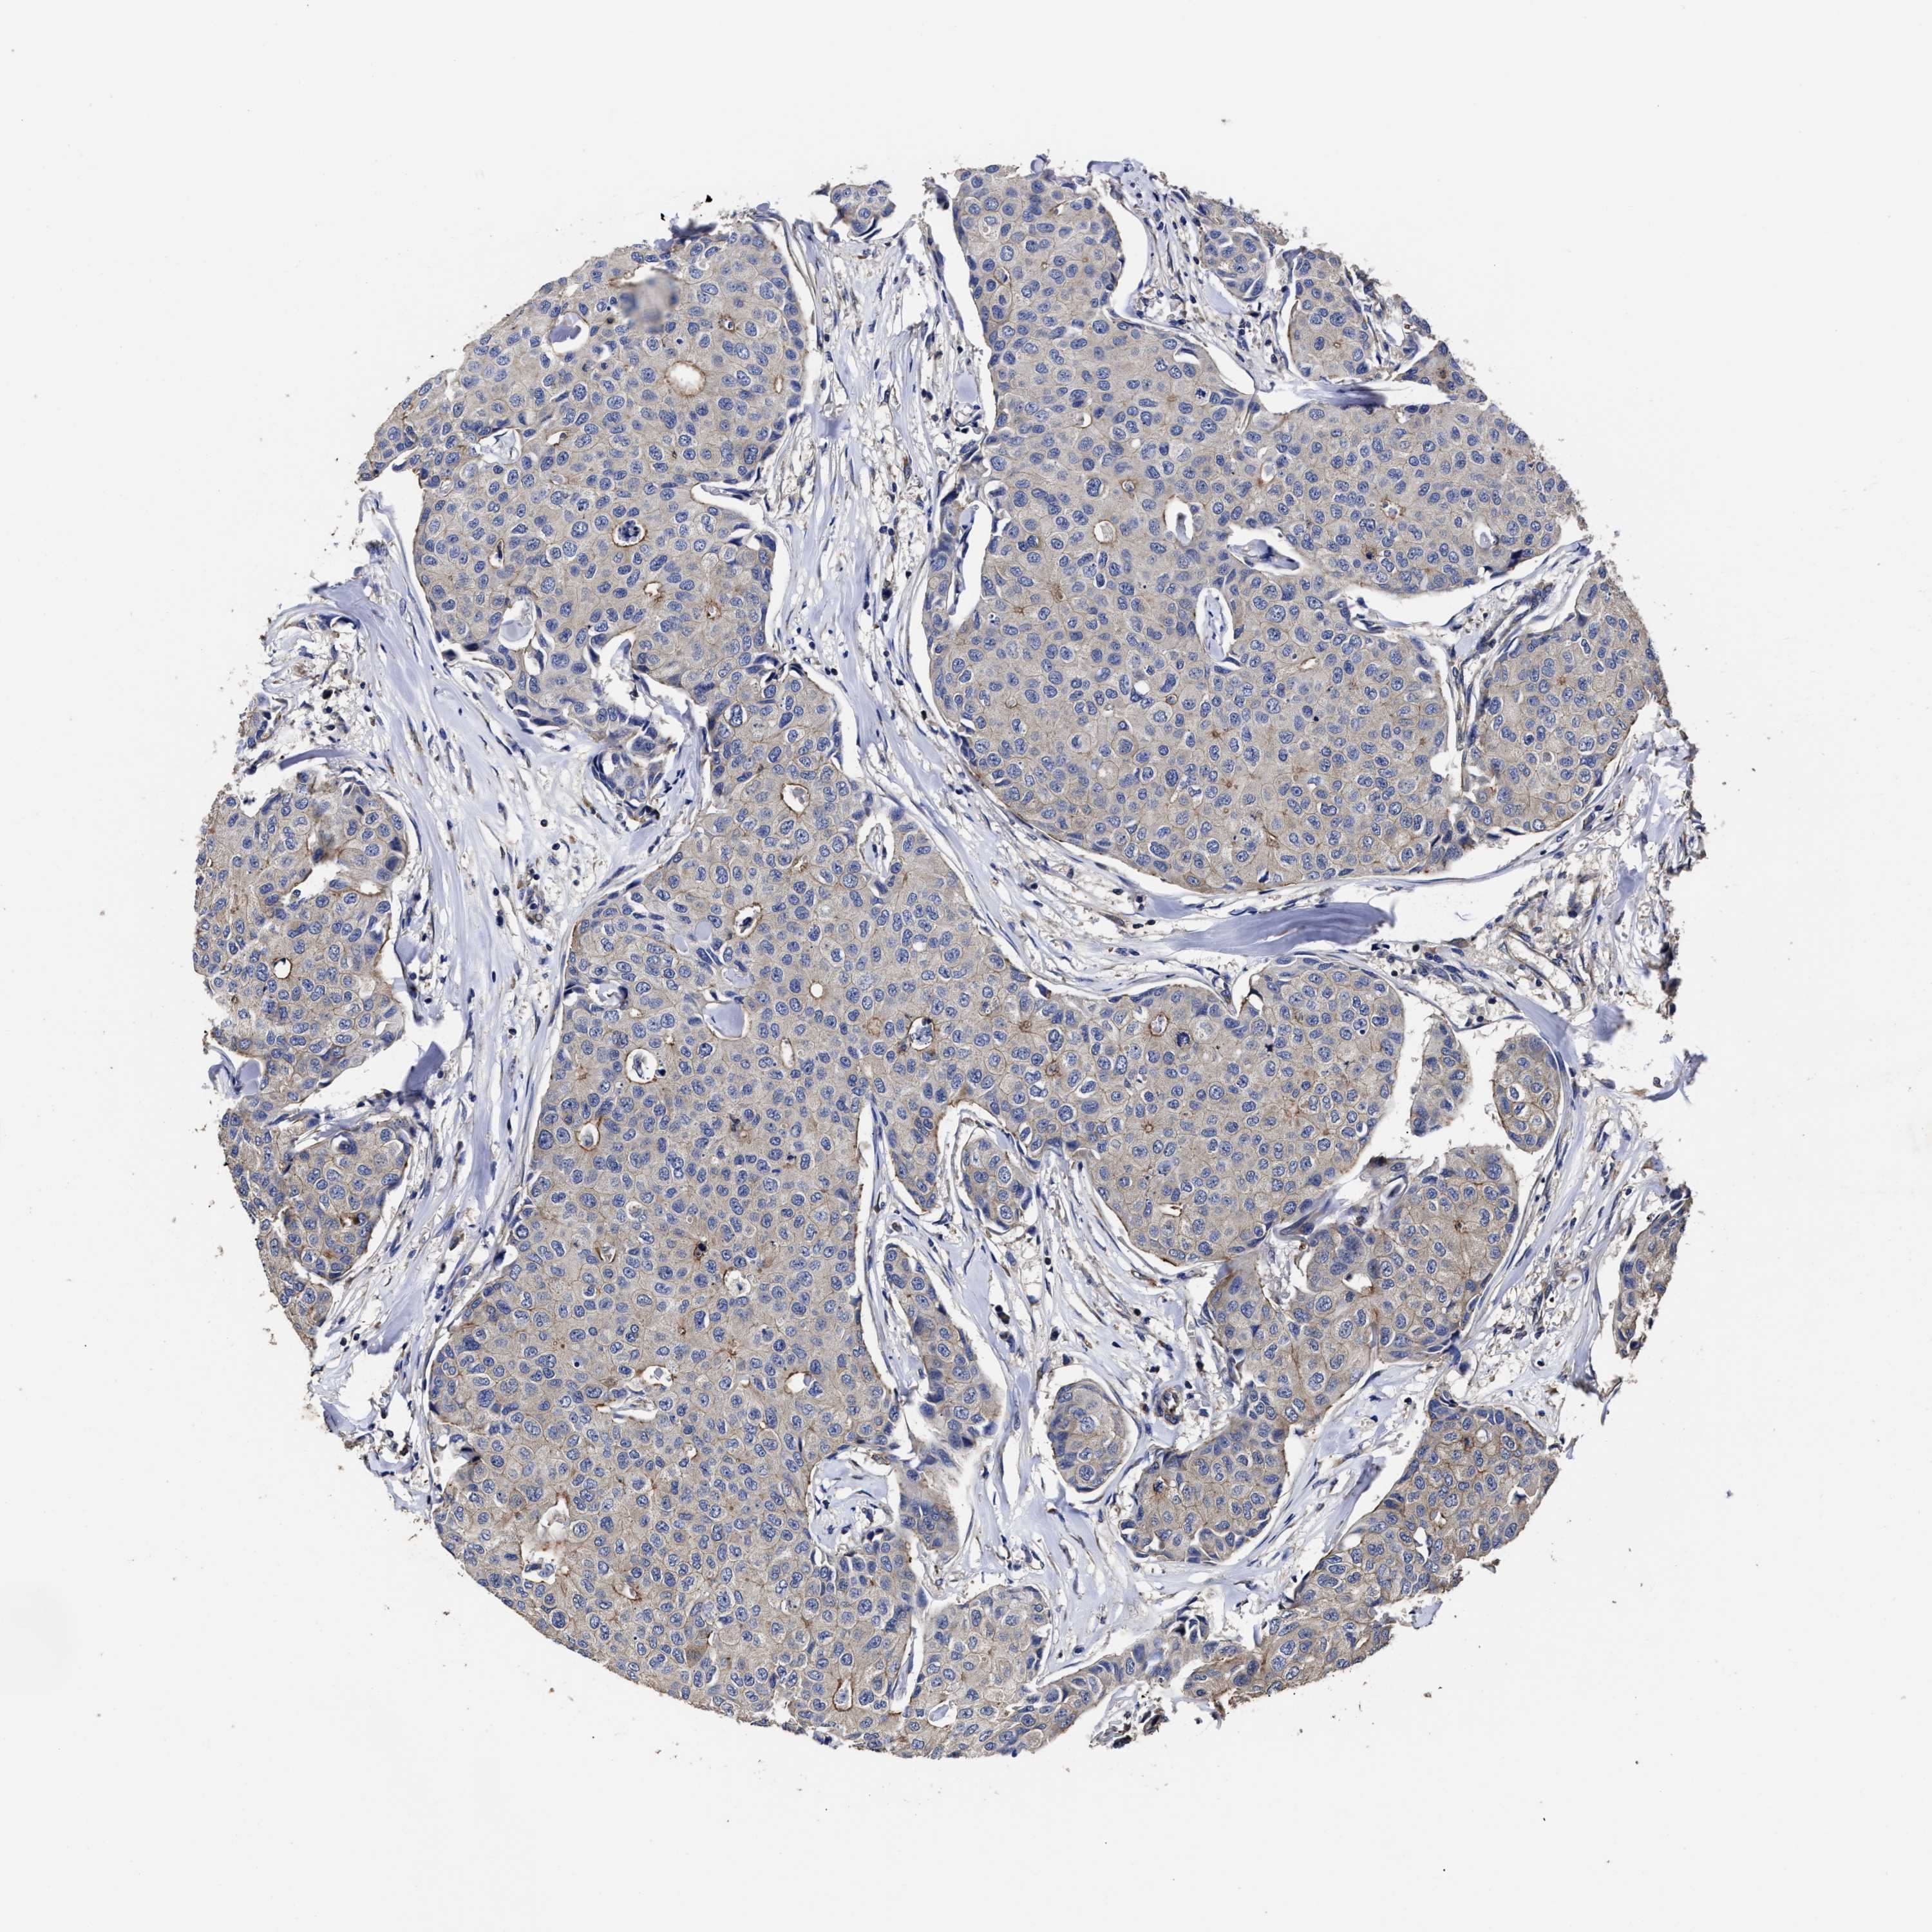

CANCER BREAST CANCER Show tissue menu

BRCA TCGA BRCA VALIDATION PROTEIN EXPRESSION